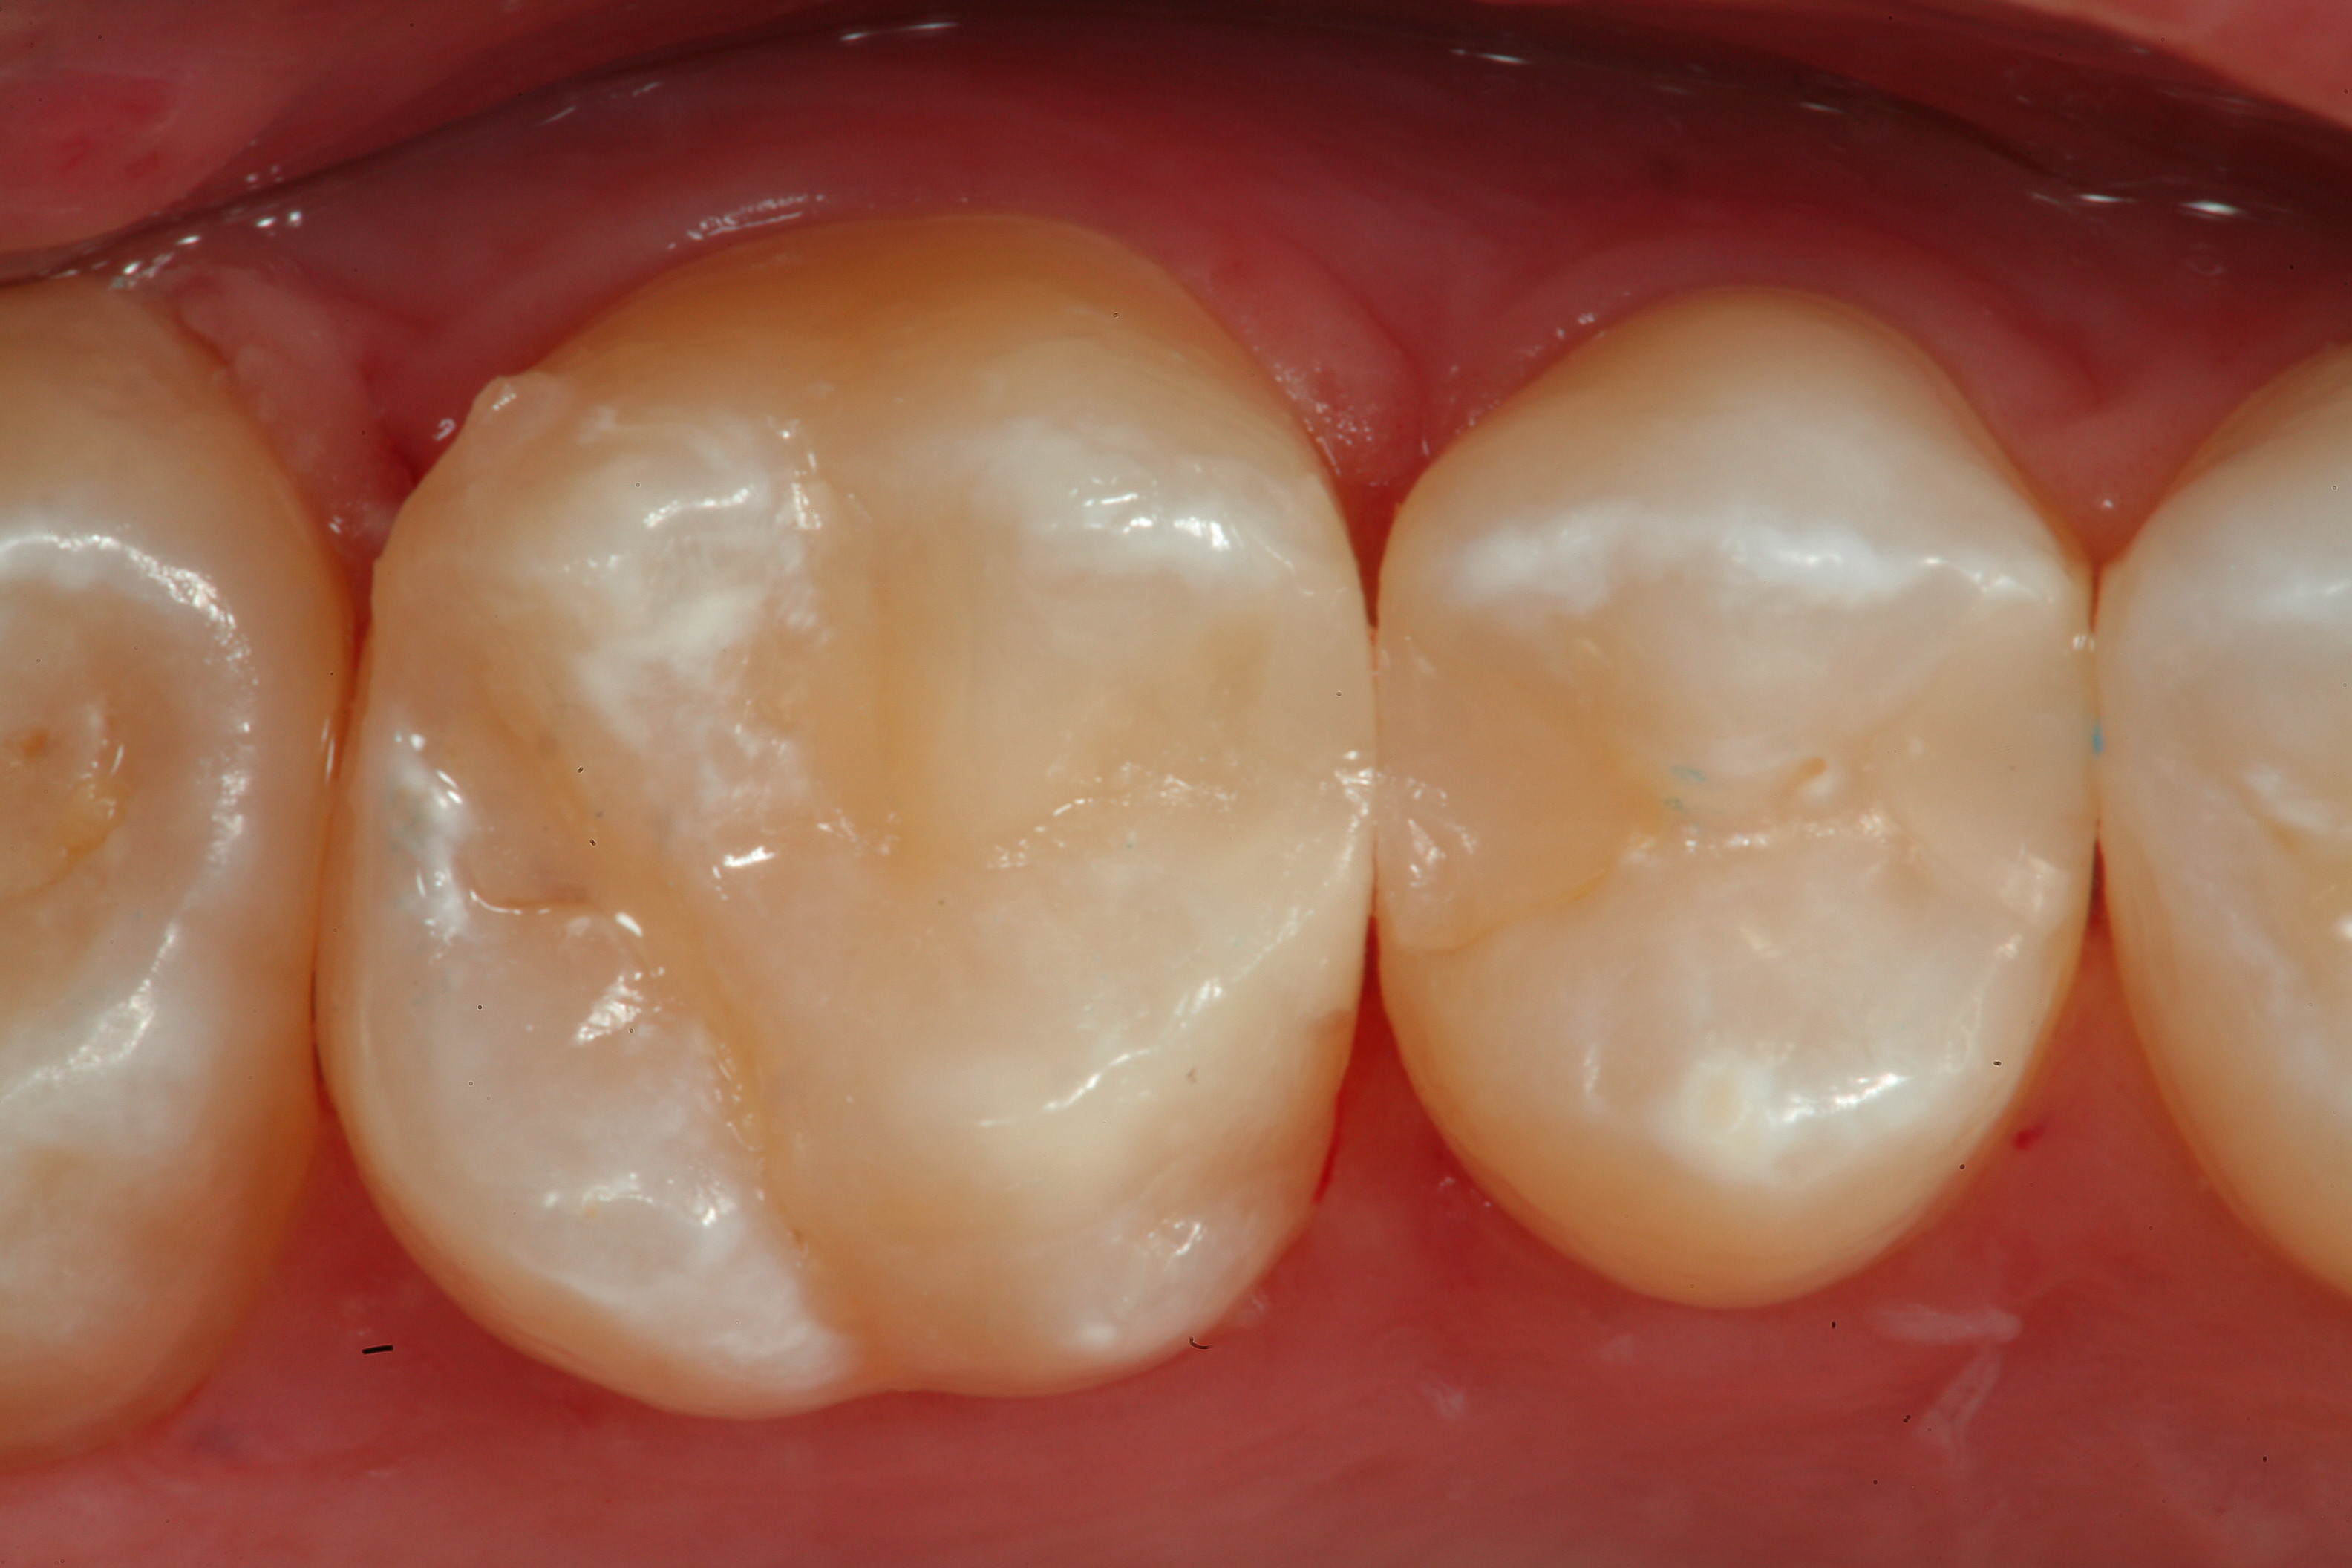

Fig 20. A distal-occlusal cavity preparation in tooth No. 29 and a mesial-occlusal-distal cavity preparation in tooth No. 30 are both shown from the occlusal aspect. A diode laser has been used interproximally to create supragingival margins to aid in precise gingival placement of the restorative material.

Figure 20